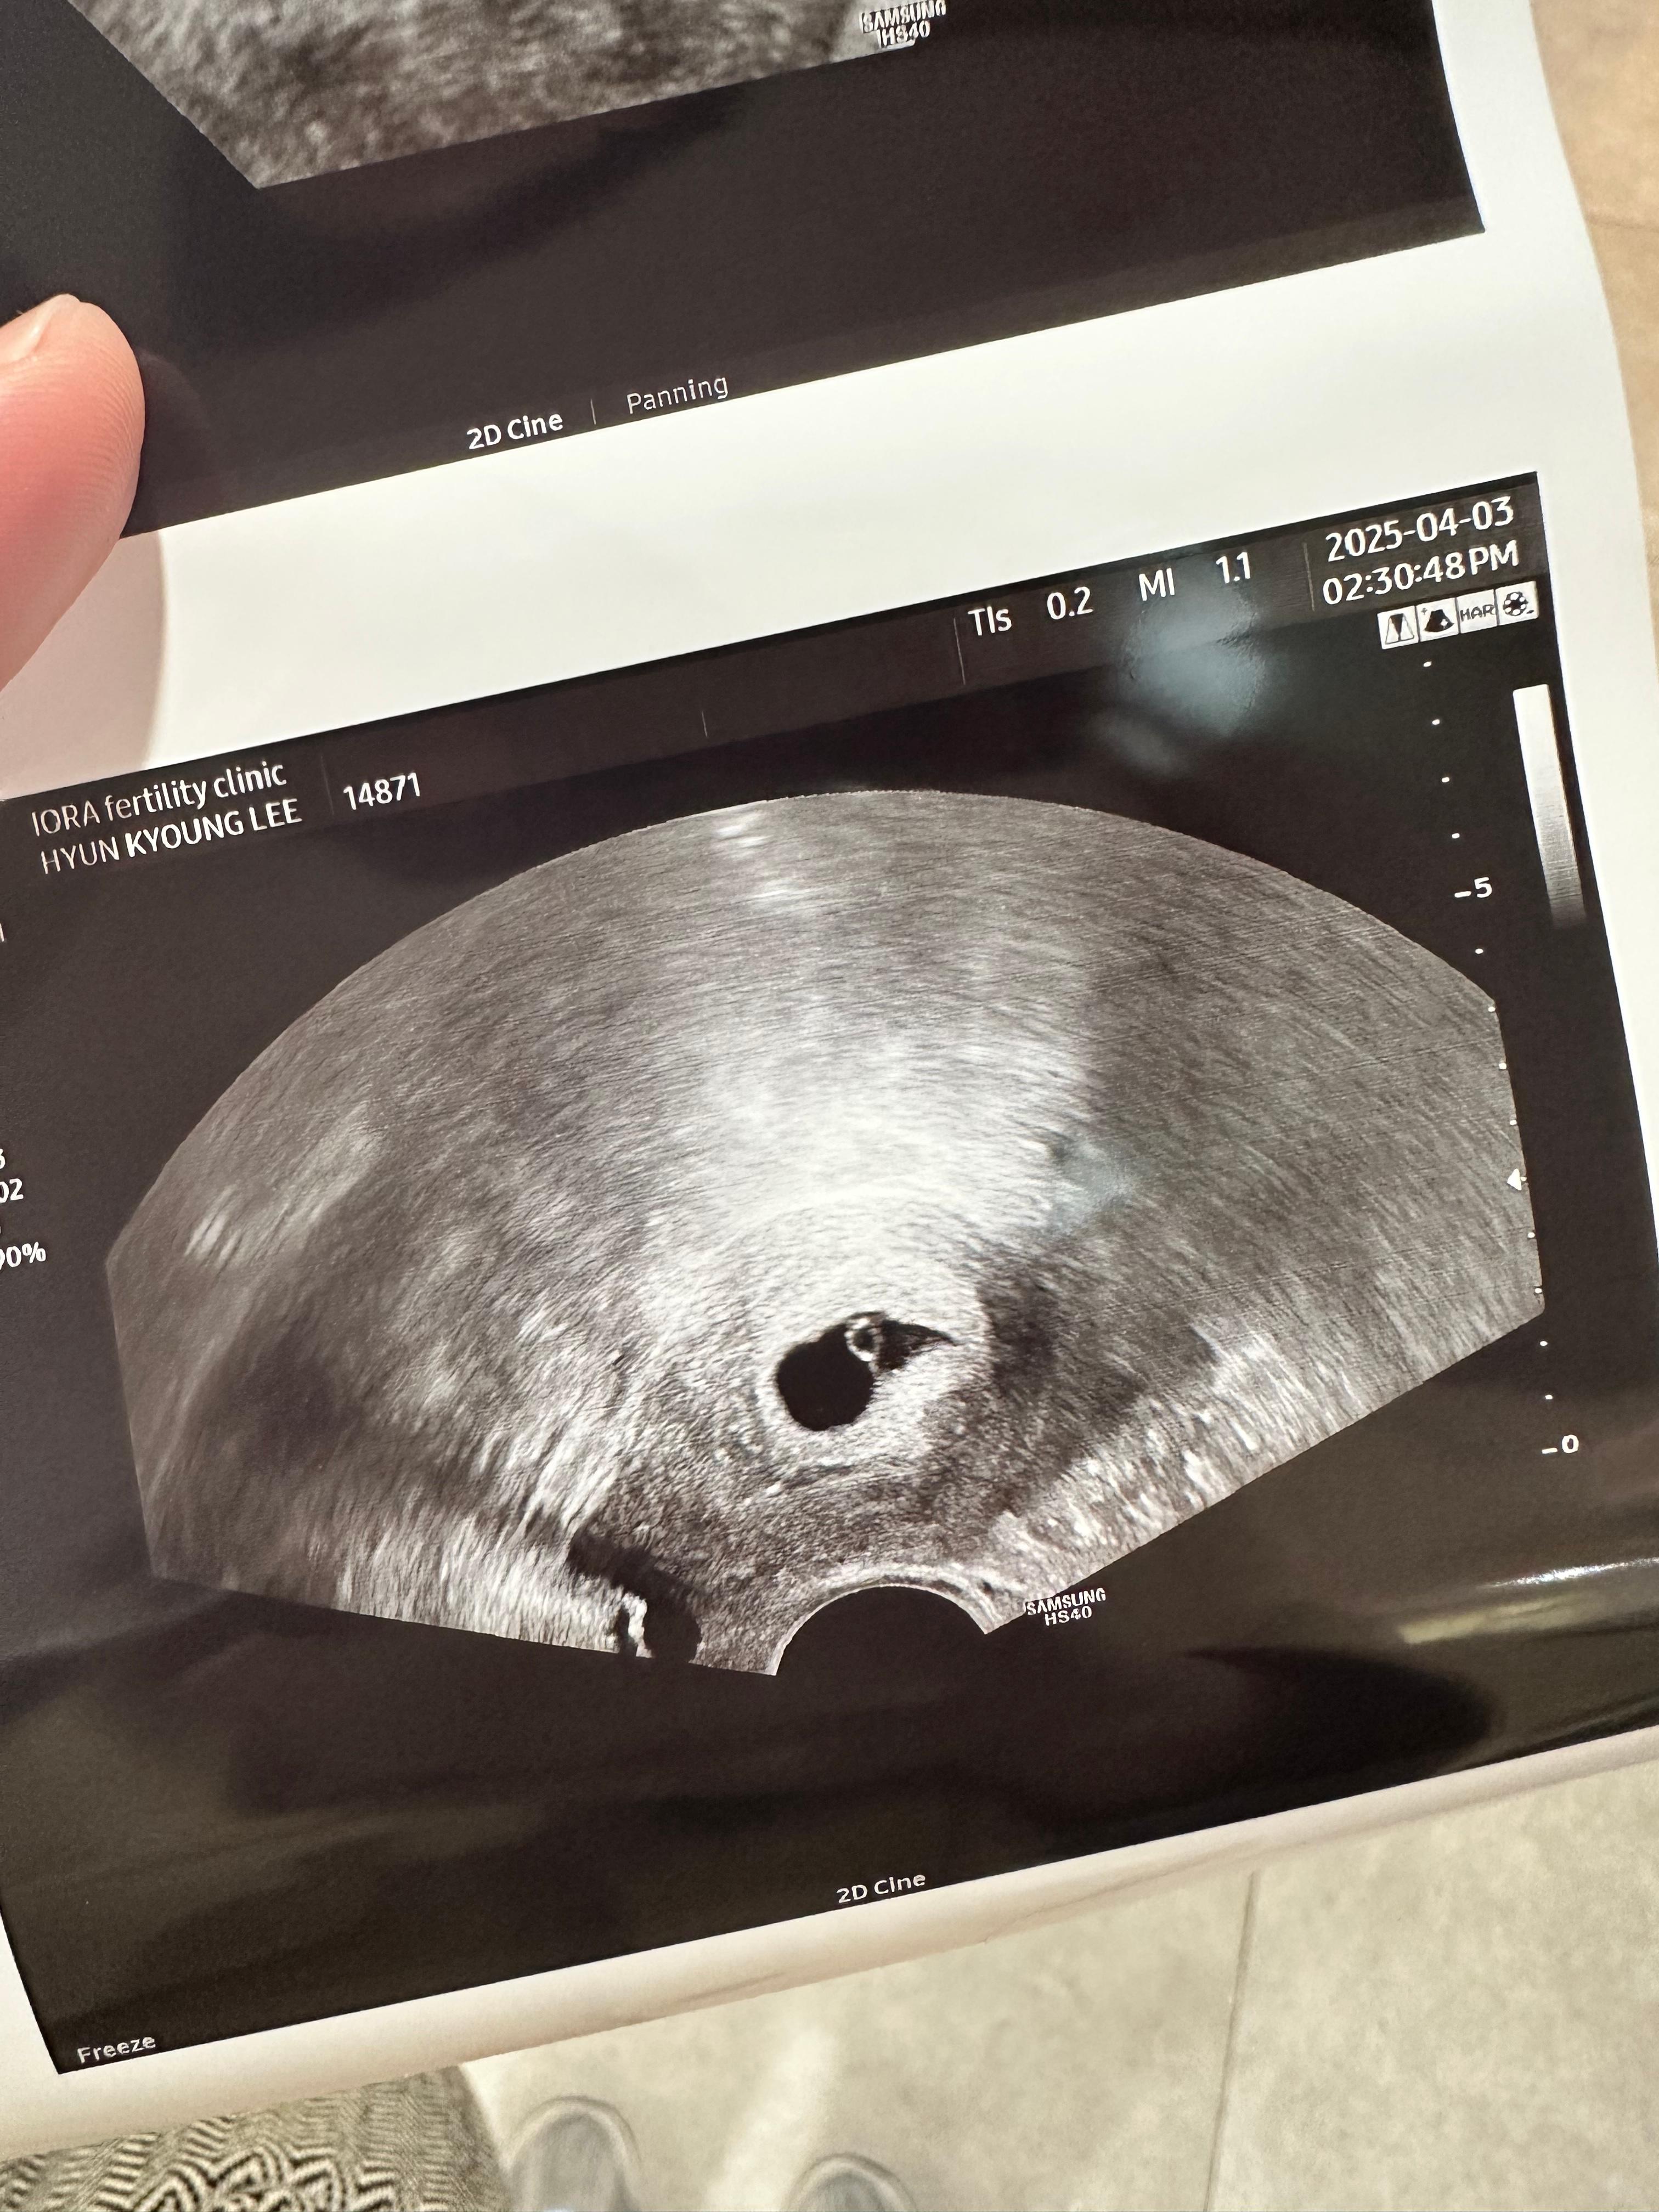

2. 임신 5주 2일차 난황 확인

이틀만에 동그란 아기집 안에 빛나는 난황이 생겼다.

높은 2차 피검수치에 쌍둥이가 아닐까 조금 기대했지만,

그건 아니었다.

그래도 뚜렷한 존재감에 왠지 안심이 되었다.

그리고 원래 진료봤던 쌤 방보다 초음파 화질이 좋은듯?